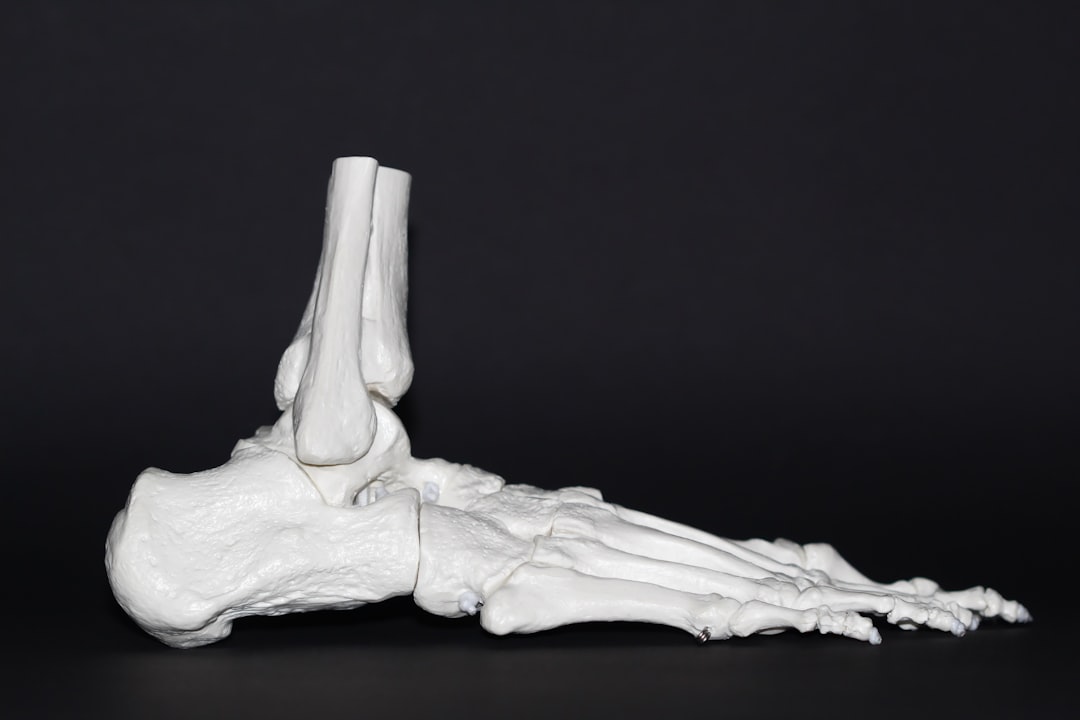

우리의 몸은 뼈로 지탱되며, 건강한 뼈는 건강한 삶의 기본입니다. 뼈가 잘 붙는 음식들은 우리가 일상에서 쉽게 접할 수 있는 것들이 많습니다. 이 글에서는 뼈잘붙는음식에 대해 깊이 있게 알아보겠습니다. 먼저, 뼈를 강화하는 이유와 뼈에 좋은 영양소를 확인해보도록 하죠! 뼈가 튼튼할수록 부상 예방에도 도움이 됩니다.

뼈 건강을 위해서는 꾸준한 운동과 함께 이러한 음식을 섭취하는 것이 중요합니다. 단순히 음식을 먹는 것만으로는 부족하니, 체중을 지탱하는 근육도 함께 키워야 합니다. 이제 어떤 음식을 통해 뼈를 강화할 수 있을지 구체적으로 살펴보겠습니다.